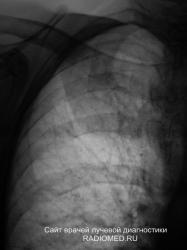

Я конечно взял на контроль с учетом того имеет место быть снижение прозрачности правой верхушки, и с учетом нашей "эпидемиологической ситуации" наточил зубы на томографию.

ОКАЗЫВАЕТСЯ - все просто - больших размеров липома, топографически там, где имеело место быть снижение прозрачности легочной ткани (на верхушке).

Самое интересное, и безусловно "козырное", что упоминания или описания, что у пациентки имеется значительных размеров липома, в амбулаторной карте нет.